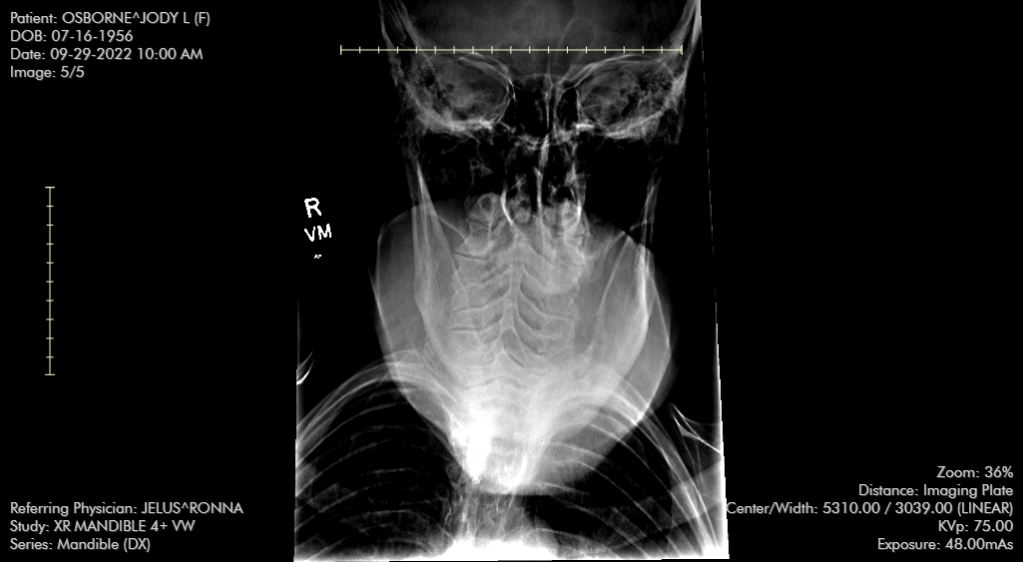

By the time I went to that appointment, most of the bruising had faded away, the ostrich egg sized bump on my forehead had reduced to a chicken sized egg bump, and I wasn’t taking OTC pain meds of any kind on a regular timeframe. My only concern was that I had what felt like a bone jutting down from my jawline as if it had been misplaced. After examining me, she suggested I get x-rays. Fortunately, there is an outpatient clinic literally right across the highway from the doctor’s office, so I went right over. I didn’t have much of a wait once I registered. X-rays were taken and I was on my way.

I have no idea how to read an x-ray, and in my lack of ability, I can’t see a single thing that shows a broken jaw, but here’s one of the five x-rays taken:

Friday morning, I got a call from the doc’s office telling me that my jawbone was broken in two places and also displaced. I needed to see an oral surgeon for further treatment.

Wow! I am so sorry you had to go through so many challenges. I was a dental radiation technician for five years. I could immediately tell your jaw was dislocated, but I had to blow it up to see the breaks. The bruising looks painful, but I am glad it did not give you more trouble than it did.